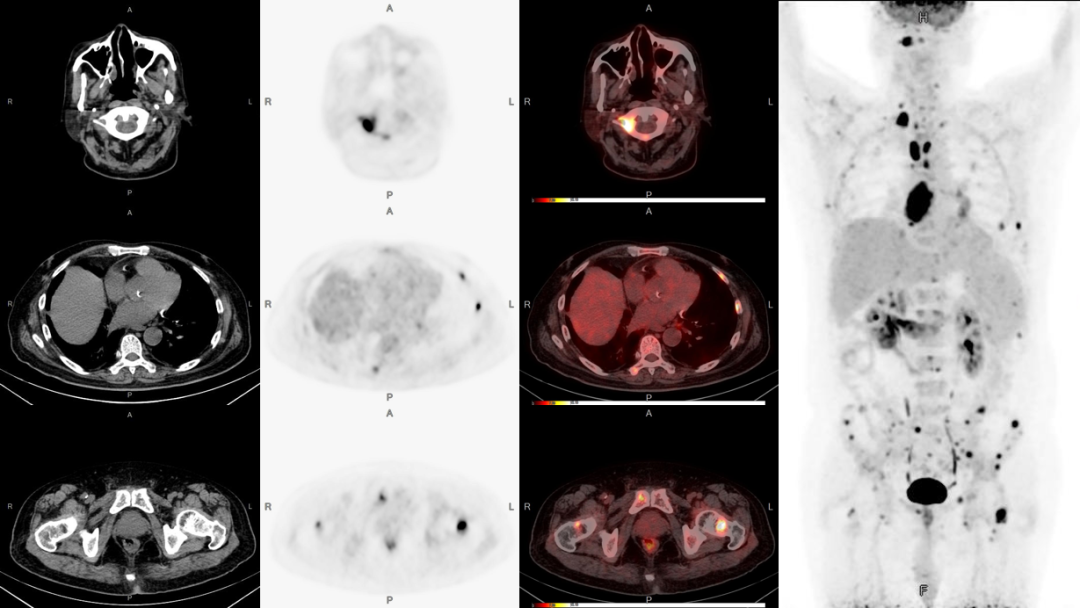

病例2:男性,51歲,復(fù)咳嗽無痰半年余;發(fā)現(xiàn)左側(cè)鎖骨內(nèi)腫塊數(shù)月。

PET/CT檢查:

1、食管上段癌伴左側(cè)鎖骨區(qū)淋巴結(jié)轉(zhuǎn)移可能;

2、縱膈及兩側(cè)肺門多發(fā)淋巴結(jié)轉(zhuǎn)移;

3、雙股骨上段轉(zhuǎn)移可能。